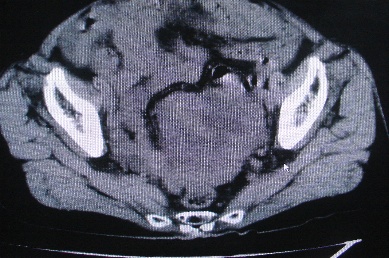

以下是引用卜一在2007-4-30 15:29:00的发言:[br]子宫明显增大,不规则,子宫壁不规则增厚,子宫腔明显缩小,子宫右侧软组织团块与子宫关系密切,内见低密度坏死区。考虑:子宫癌并周围侵润。